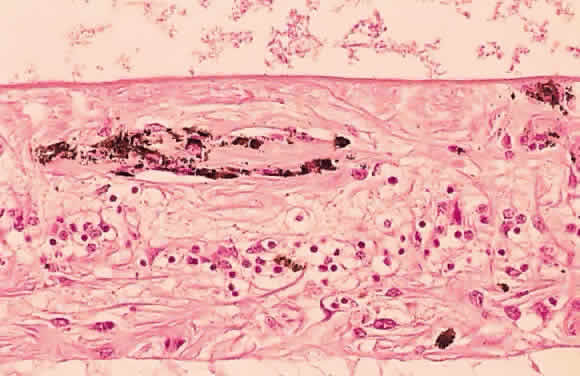

Fig. 17. A. A histologic section stained with H & E demonstrating vascularized

membranes on the disc and retina. Tractional retinal detachment is present. Notice

the subretinal fluid (amorphous eosinophilic material). B. Fundus photograph of fibrous tissue emanating from the disc in patient

with proliferative diabetic retinopathy. The disc is pale; the macula

is edematous with exudate. Pigmented laser spots are visible temporally. Fig. 17. A. A histologic section stained with H & E demonstrating vascularized

membranes on the disc and retina. Tractional retinal detachment is present. Notice

the subretinal fluid (amorphous eosinophilic material). B. Fundus photograph of fibrous tissue emanating from the disc in patient

with proliferative diabetic retinopathy. The disc is pale; the macula

is edematous with exudate. Pigmented laser spots are visible temporally.